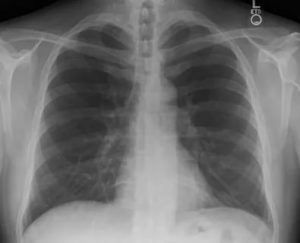

Чтобы понимать, на что делается акцент врачом-рентгенологом, нужно знать описание рентгенограммы здорового человека:

- Отсутствие участков затемнения по всем легочным полям.

- Корни структурны.

- Границы диафрагмы не изменены.

- Средостение обычных размеров.

- Реберно-диафрагмальные синусы без особенностей.